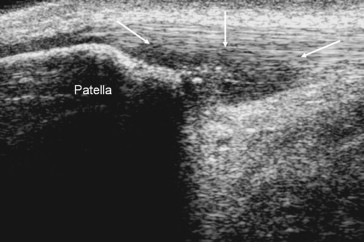

US imaging can partly evaluate the femoropatellar cartilage, its thickness and trochlear femoral and patellar angle [19,20] (Fig. 8).

Fig. 8.

Femoropatellar pain syndrome. Transverse US scans right over the superior patellar pole, with flexed knee, in a normal boy. The image allows evaluation of the femoropatellar cartilage, hypoechoic, thickness (A) (white lines) and trochlear femoral and patellar angle (B).